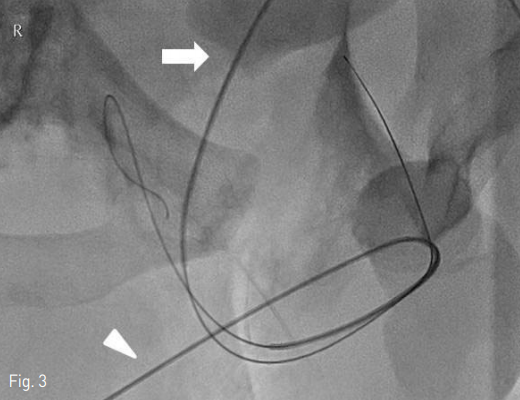

양측 속장골동맥과 그 분지들에서 기인하는 동맥 출혈에 대한 색전술을 시행한 후 요도재배열술을 시작함. 먼저 이전 거치되어 있던 요도관을 제거하고 5 Fr catheter (KMP, Cook, Bloomington, Indiana)를 요도 입구에 삽입한 다음, 2% 리도카인 10mL를 카테터 내로 주입하고 역행성 요로 조영술을 시행하였을 때 전립선-막양부 요도 파열과 조영제 유출 소견이 확인됨 (Fig. 2). 0.035-inch guidewire (Terumo, Tokyo, Japan)와 카테터를 이용하여 손상된 요도를 지날 때까지 조정하였으나, 조영제로 확인하였을 때 완전 파열된 요도의 바깥 자유공간으로 카테터가 반복적으로 나가는 양상임. 이에 환자의 치골상방 부위에서 초음파 유도하에 21 gauge Chiba needle로 방광을 천자하였음. 0.035-inch guidewire (Terumo)와 5 Fr catheter (KMP, Cook)를 방광 내에 거치시키고 이전 혈관조영술로 인한 조영제를 흡인, 생리식염수로 희석시켜 시야를 확보하였음. 그 후 guidewire와 카테터를 이용하여 순행성 요로의 진관강 (true lumen)을 찾기 위한 조정을 하였으나 역시 많은 확률로 완전 파열된 요도의 바깥 자유공간으로 나가는 양상임. 이에 이전 역행성 요로로 넣어 놓은 카테터를 경계표 (landmark)로 삼아 전후상, 경사상 영상을 확인하면서, 치골 상부 방광루를 통한 순행성 guidewire를 파열된 부분을 지나, 전부요도의 진관강을 통해 바깥요도구멍으로 통과시키는데 성공함 (Fig. 3). Guidewire의 through-andthrough technique으로 치골상부로부터 바깥요도구멍까지의 경로를 확보한 상태로, 카테터를 바깥요도구멍에서 치골상부까지 삽입하고 guidewire의 soft tip 과 hard tip의 방향을 바꾸었음. 바깥요도구멍쪽으로 나와 있는 guidewire의 hard tip쪽으로, 미리 끝 부분에 18 gauge 바늘로 구멍을 내어 놓은 16 Fr 요도관을 삽입하여 방광 내에 거치하는데 성공함 (Fig. 4).

Fig 3

Supported by the 5 Fr catheter, a 0.035-inch guidewire (arrowhead) was located in free-space in pelvic cavity without finding the disrupted contralateral proximal urethra (Retrograde approach). Other 0.035-inch guidewire (arrow), which was loaded in the 5 Fr catheter, was passed through the suprapubic cystostomy and was navigated to pass through the site of posterior urethral disruption so to reach the external urethral orifice (antegrade approach).